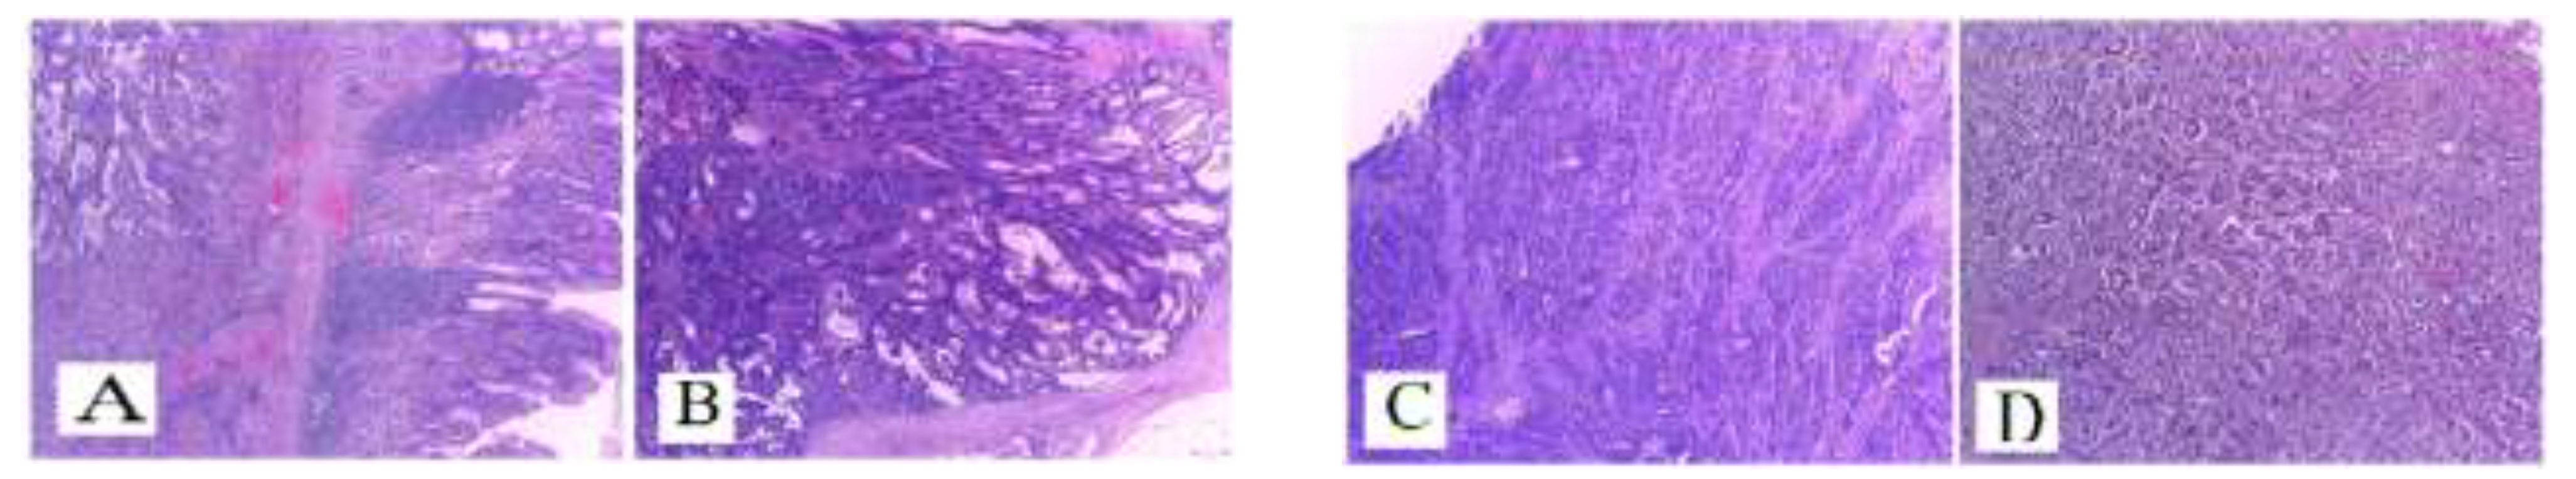

Case presentation

Mismatch repair (MMR) genes and Microsatellite instability (MSI)

Clinical and prognostic features of MSI-H colorectal tumors